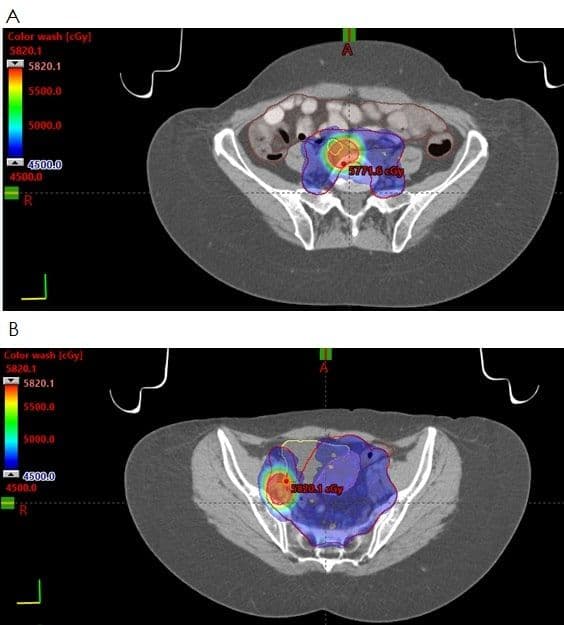

Adenocarcinoma in situ (AIS) is the precursor of invasive endocervical adenocarcinoma. Microscopically, AIS has preserved endocervical gland architecture (Figure 10) but with varying degrees of atypia (e.g., nuclear enlargement and stratification, nuclear hyperchromasia, apical mitotic figures, and basal apoptoses) (Figure 11A, 11B).

Figure 10

Figure 11

Partial gland involvement by AIS is common and can be highlighted by positive p16 immunostaining in the lesional cells (Figure 12A, 12B). AIS is most commonly identified at the transformation zone and may spread up to 3 cm upward in the endocervical canal [83]. Importantly, AIS may be multifocal, and it is not unusual to find residual tumor after negative conization margins [84].

Figure 12

Most endocervical adenocarcinomas are of usual type, characterized by predominantly glandular, papillary, and/or cribriform architecture, diminished cytoplasm (often with a deep red hue), hyperchromatic nuclei, prominent apical nuclei, and basal apoptoses, as seen in AIS. Growth patterns may be expansile (Figure 13), infiltrative with stromal desmoplasia (Figure 14A, 14B), or mixed.  Usual-type endocervical adenocarcinoma is almost invariably HPV-associated, and HPV infection can be definitively demonstrated in the vast majority of cases.

Figure 13

Figure 14